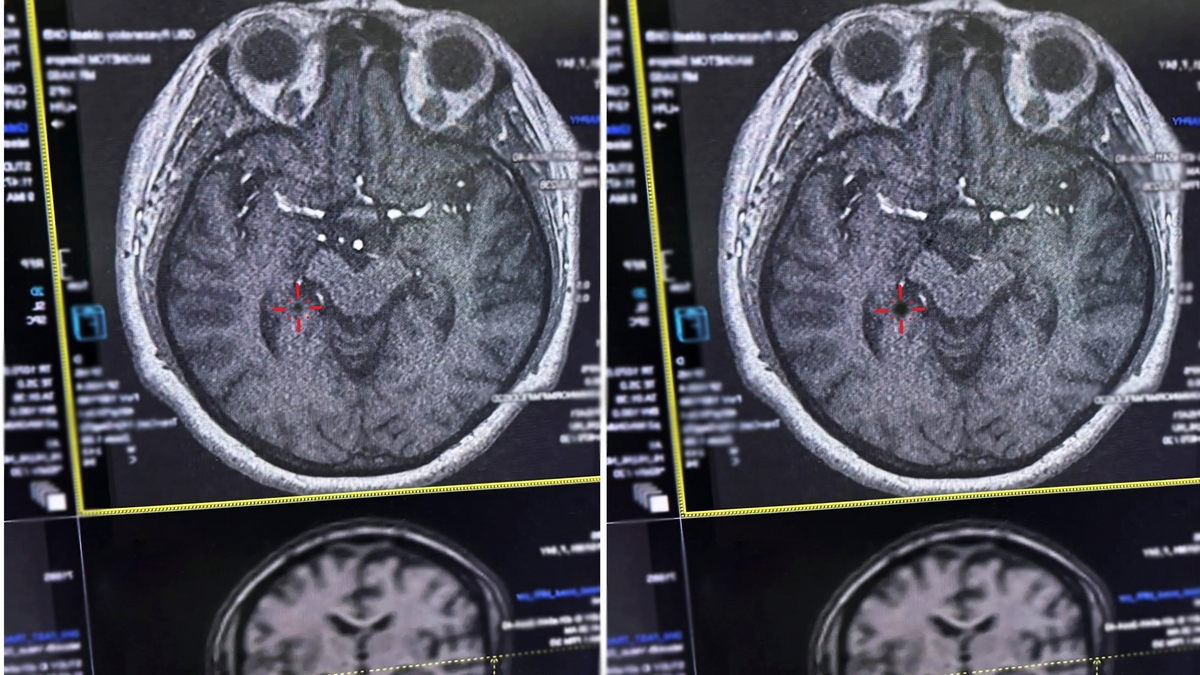

Врачи Рязанской ОКБ спасли женщину с инсультом

Врачи Рязанской областной клинической больницы спасли женщину с инсультом. Об этом сообщила пресс-служба министерства здравоохранения региона.

Пациентка попала в больницу из магазина, где ей стало плохо. У рязанки закружилась голова и она потеряла сознание. У женщины была обездвижена правая сторона тела, сильно болела голова. Медики смогли помочь пациентке в первые 4,5 часа после начала инсульта – они успели в так называемое «терапевтическое окно».

Фото: министерство здравоохранения Рязанской области